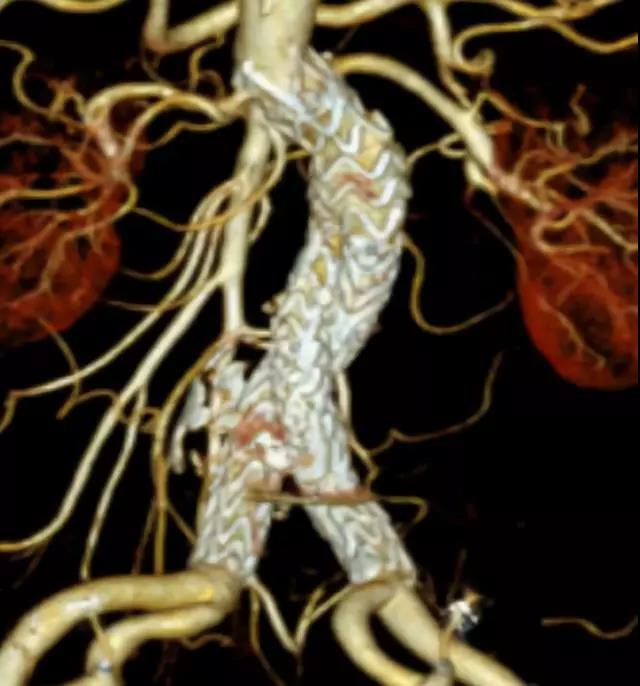

此次研究,纳入腹主动脉瘤的最大直径为85mm,平均直径为50.78mm;最短瘤颈长度为11mm,平均长度为31.34mm;最大肾下成角为74.6度,平均角度为32.48度。从动脉瘤最大直径变化来看,经过腹主动脉腔内治疗后,在出院前和术后6个月都有所减小。 在此次研究中,先健Yuranos™新一代腹主动脉覆膜支架系统临床试验初步展现了优秀的临床试验结果,其30天内MAE发生率低,安全性得以验证;而且由于该产品的柔顺性有较大提升,输送器直径减小,对于短瘤颈和角度大的病例是更好的选择。 入组病例展示: 病例一:男性,年龄69岁,既往高血压,糖尿病病史。术前腹主动脉瘤直径67.3mm,近端瘤颈长度23.2mm,近端锚定区直径21.2mm,肾下成角60.5度。 术中从右侧股动脉穿刺,选用先健型号为AB-2412-50-120的主体支架,支架近端定位于右肾动脉开口处,后释放打开裸支架,并向下释放主体短分支,左侧输送进入先健髂动脉延长支架IE-1416-100,并释放,保留左侧髂内动脉。接着释放主体长分支,右侧输送进入先健髂动脉延长支架IE-1424-80,并释放,保留右侧髂内动脉。 手术顺利,无内漏,持续时间1小时10分钟。术后CTA检查,支架形态良好,无内漏。详见下图: 术前影像 术中影像 出院前影像 术后6个月影像 术后1年影像 病例二:女性,年龄72岁,既往高血压,静脉曲张病史。术前腹主动脉瘤直径48.81mm,近端瘤颈长度16.15mm,近端锚定区直径18.43mm,肾下成角66度。 术中从右侧股动脉穿刺,选用先健型号为AB-2412-50-140的主体支架,支架近端定位于右肾动脉开口处,后释放打开裸支架,并向下释放主体短分支,左侧输送进入先健髂动脉延长支架IE-1414-120,并释放,保留左侧髂内动脉。接着释放主体长分支,右侧输送进入先健髂动脉延长支架IE-1414-80,并释放,保留右侧髂内动脉。

手术顺利,无内漏,持续时间1小时10分钟。术后CTA检查,支架形态良好,无内漏。详见下图:

术前影像

术中影像

出院前影像